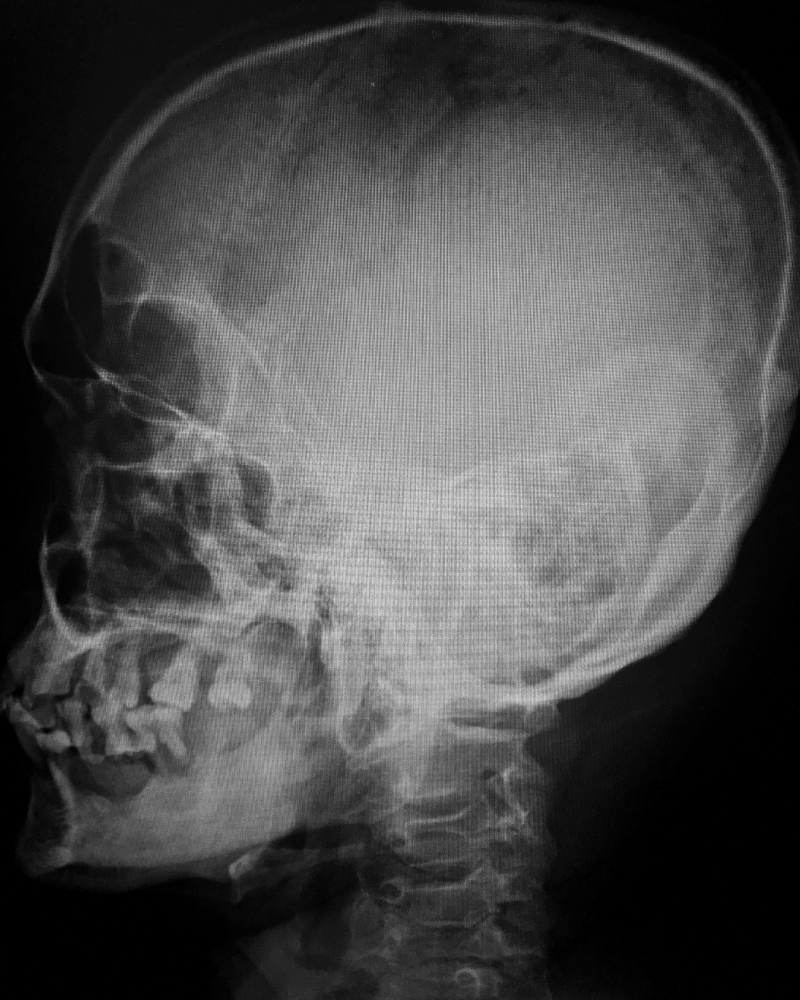

¿Estás buscando información sobre el precio de neurocirugía para hidrocefalia y deseas una opción accesible y transparente? ¡Estás en el lugar correcto! En nuestra clínica, nos comprometemos a proporcionarte detalles claros sobre los costos de este procedimiento. Con la experiencia del Dr. Alejandro Ventura Rendón, un especialista en neurocirugía para hidrocefalia, te garantizamos una atención de calidad a un precio justo. Contáctanos hoy mismo para obtener más información y dar el primer paso hacia tu bienestar neurológico.

Soy médico especialista en cirugía neurológica y columna vertebral, con la experiencia profesional en el uso de la tecnología más innovadora a nivel mundial.